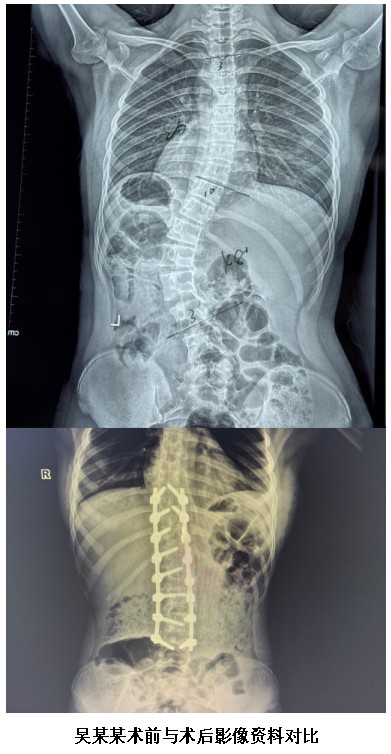

患者吳某,女,15歲,因“發(fā)現(xiàn)存在高低肩1月”入院。入院查體顯示生命體征平穩(wěn),心肺腹未見明顯異常,右側(cè)肩部較左側(cè)稍高,脊柱棘突胸段向右側(cè)偏移、腰段向左側(cè)偏移。完善檢查后提示:雙肺少許纖維灶,胸、腰椎側(cè)彎;心電圖顯示竇性心律不齊,心臟彩超未見明顯結(jié)構(gòu)及功能異常;血常規(guī)、肝腎功能電解質(zhì)、血氣分析、凝血功能均正常,胸腰椎CT及全脊柱MRI未見脊髓空洞。醫(yī)生診斷為脊柱側(cè)彎畸形,經(jīng)MDT多學科會診評估,具備明確手術條件,擬為患者進行脊柱側(cè)彎畸形矯形手術。

得益于術前精準規(guī)劃與術中精細操作,本次手術全程出血量少、安全可控,有效減少手術創(chuàng)傷與輸血風險,實現(xiàn)了精準、微創(chuàng)、安全的手術目標。經(jīng)過數(shù)小時精細操作,手術圓滿成功,患者脊柱畸形得到顯著矯正,身姿恢復挺拔,術后生命體征平穩(wěn),安返ICU繼續(xù)觀察治療。